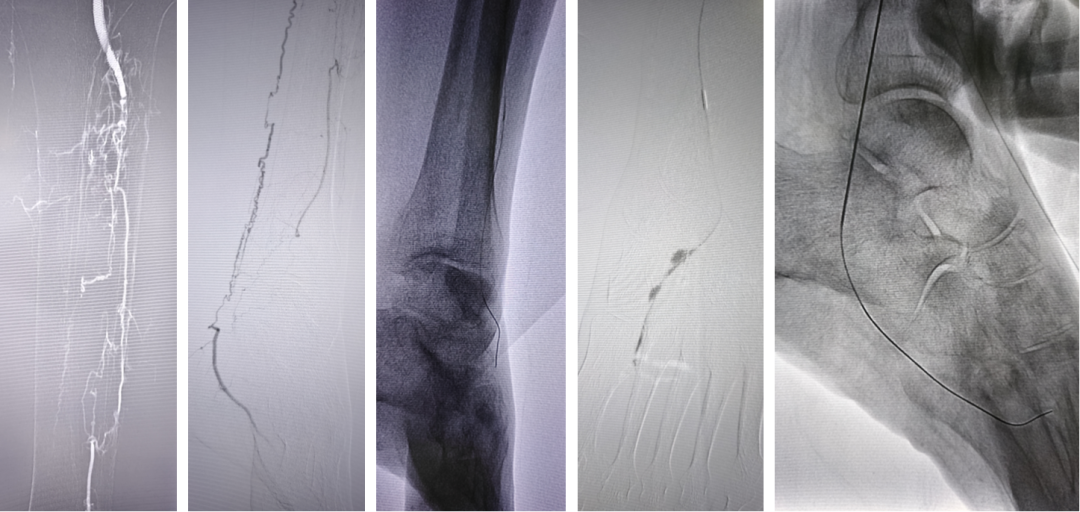

★ 经足弓逆向开通胫前动脉

Case 3:一例腘动脉闭塞患者,胫前动脉远端不显影,足底动脉仅通过侧支隐约可见。术者选择顺穿足底动脉,导丝经足弓上行,成功进入胫前动脉真腔,建立轨道后完成球囊扩张,恢复足弓血流,术后1个月患者溃疡愈合。